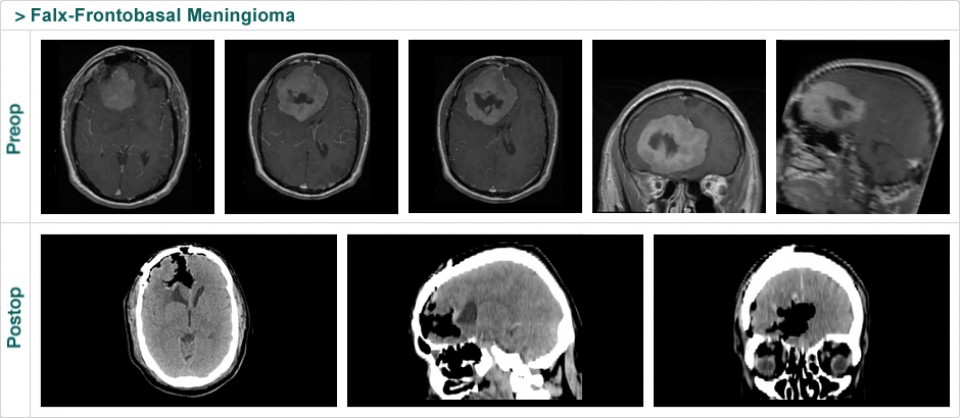

Dr. Attia is an attending neurosurgeon and the director of skull base surgery service in the department of neurosurgery at Sheba Medical Center in Tel HaShomer. His specialty focuses on skull base and cerebrovascular neurosurgery.